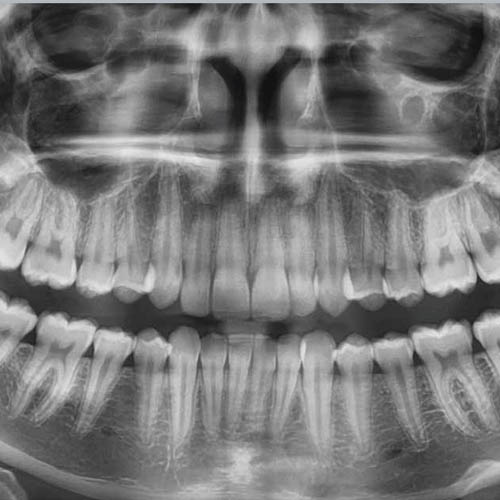

- Karijes zuba, oboljenja desni

Ako se dentalna oralna higijena ne održava redovno. Ako se ne peru zubi i ako se ne koristi zubni konac.

Ostaci hrane se zadržavaju uzrokujući proizvodnju bakterija između zuba, oko desni i na jeziku.

Problemi sa zadahom mogu nastati i usled lošeg naleganja dentalnih nadoknada kao što su krunice i mostovi, ili nastankom karijesa

Kariozni i polomljeni zubi, zaostali korenovi i parodontalni džepovi odlično su mesto za zadržavanje hrane, koja se vremenom raspada što stvara vrlo neugodan miris.